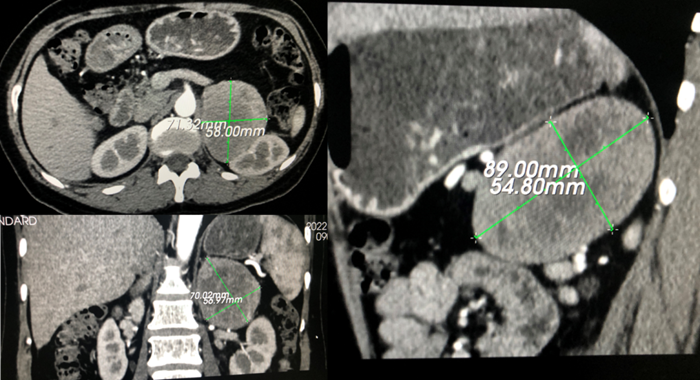

近日,江西省人民医院(南昌医学院第一附属医院)泌尿外科团队在麻醉科的密切配合下顺利完成了一台高风险、高难度手术——腹腔镜下肾上腺肿瘤切除手术,成功切除了一个直径约9cm的罕见巨大嗜铬细胞瘤,为患者拆除了埋在体内的“不定时炸弹”,帮助患者重获健康。

术前CT

该肿瘤体积约89mmx54.8mmx71.32mm,血供丰富,位置很特殊,肿瘤紧贴左肾、左肾动脉、左肾静脉、中央静脉、脾动脉、脾脏、胰腺、肾脏、膈肌等组织器官,术中损伤任何一个血管都有可能导致大出血,损伤任何一个器官都可能需要同时切除该器官。而且该肿瘤内部有出血坏死等液体,并非完全实性肿瘤,由于肿瘤体积大,周围没有间隙,为了切除肿瘤,术中如果过多用力挤压肿瘤不仅会导致患者血压剧烈上升,而且容易造成肿瘤破裂,肿瘤一旦破裂,万一肿瘤为恶性将导致肿瘤种植转移,术后容易复发。